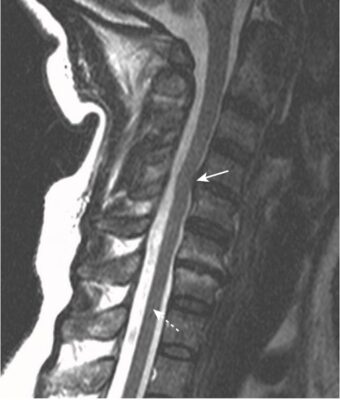

- Ở cột sống cổ, thoát vị đĩa đệm xảy ra thường gặp nhất ở C4-C5, C5-C6 và C6-C7 (Hình 5).

- Trên MRI, đĩa đệm thoát vị thường là phần lồi ra không đối xứng, khu trú của chất liệu đĩa đệm cường độ thấp, vượt ra ngoài giới hạn của vòng xơ (Hình 6).